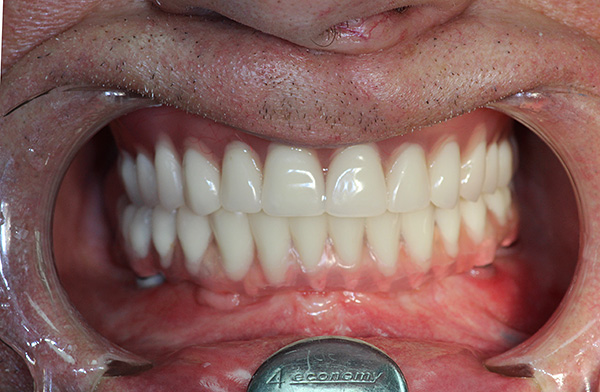

A sogra passou pela implantação completa de 7 dentes da mandíbula superior na ausência dos dentes, ajudamos com o dinheiro. Eles colocam modernos implantes israelenses do IIA, comparáveis aos suíços, mas não tão caros. Percebo imediatamente que a sogra não podia usar uma mandíbula falsa devido ao reflexo do vômito; portanto, a solução estava apenas nos implantes.O procedimento em si foi indolor, sob anestesia local. Após a implantação, tudo se curou rapidamente e sem dor. Em quatro semanas todas as coroas foram instaladas. A sogra diz que ela se acostumou com dentes novos por cerca de um mês e agora os sente completamente como parentes. Ele está especialmente feliz por poder comer maçãs novamente. E estamos felizes por ela por não termos nos confundido com implantes e um médico. Estamos felizes que tudo correu bem.